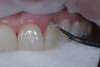

Then, the restorations for teeth Nos. 8 and 9 were created. Minimal augmentation would be required to improve the patient’s smile. The opaque shade was layered slightly irregularly to mimic the appearance of the patient’s natural dentition, particularly the interplay of the enamel and dentin optical properties (Figure 4). A putty matrix was inserted to guide composite placement when augmenting the shape and length of the central incisors using the CL composite (Figure 5). Then, a small amount of CL composite was applied as the final layer (Figure 6) and cured, after which a final polish was performed.

Fig 4. The opaque composite shade was layered slightly irregularly to mimic the optical properties of the patient’s natural dentition.

Figure 4